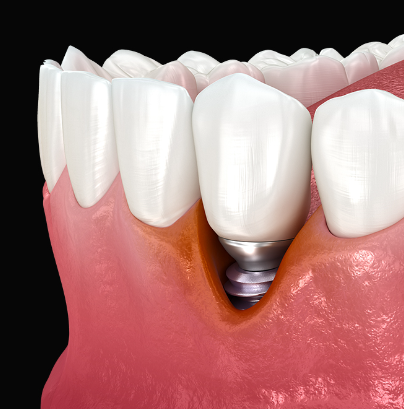

아리임플란트는

구조 자체가 다릅니다.

잇몸뼈가 아닌 단단한 기저골에 식립해서

풍치가 있어도, 뼈가 얇아도

안정적으로 고정될 수 있습니다.

나사선이 아래쪽 깊은 곳에 위치해

잇몸이 내려가도

금속 부분 노출 위험도가 적어지죠.

그리고 치조골 흡수에 영향 덜 받기에

10년 이상 장기 안정성

매우 뛰어나다고 할 수 있습니다.

발치 당일에도 당일 식립 +

당일 임시치아 장착이 가능하기에

비어 있으면 안 되는 전치부는

큰 장점이죠.